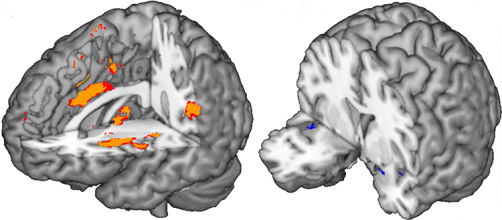

Quand la colère gronde, notre cerveau se met en alerte

Pas de futur pour les égoïstes, révèle leur cerveau

Voix et émotions : la clé est dans le front